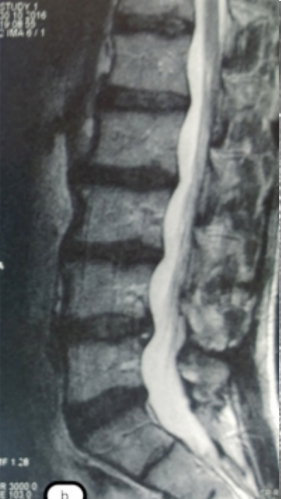

Грыжа Диска L4-L5

3 процедуры ФДТ, 9 процедур MBST

Параметры изменяются в зависимости от процедуры

Дата публикации: 22.08.2025 14:27:20